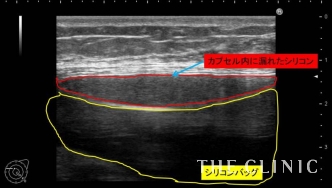

エコー検査では左右共にシリコンバッグが破損していることが判明。こちらは左胸のエコー画像ですが、シリコンバッグ自体は破損して変形、被膜内にバッグの内容物が漏れ出しているのが確認できます。そのことで、コヒーシブタイプではなく、シリコンジェルのバッグであることが分かりました。